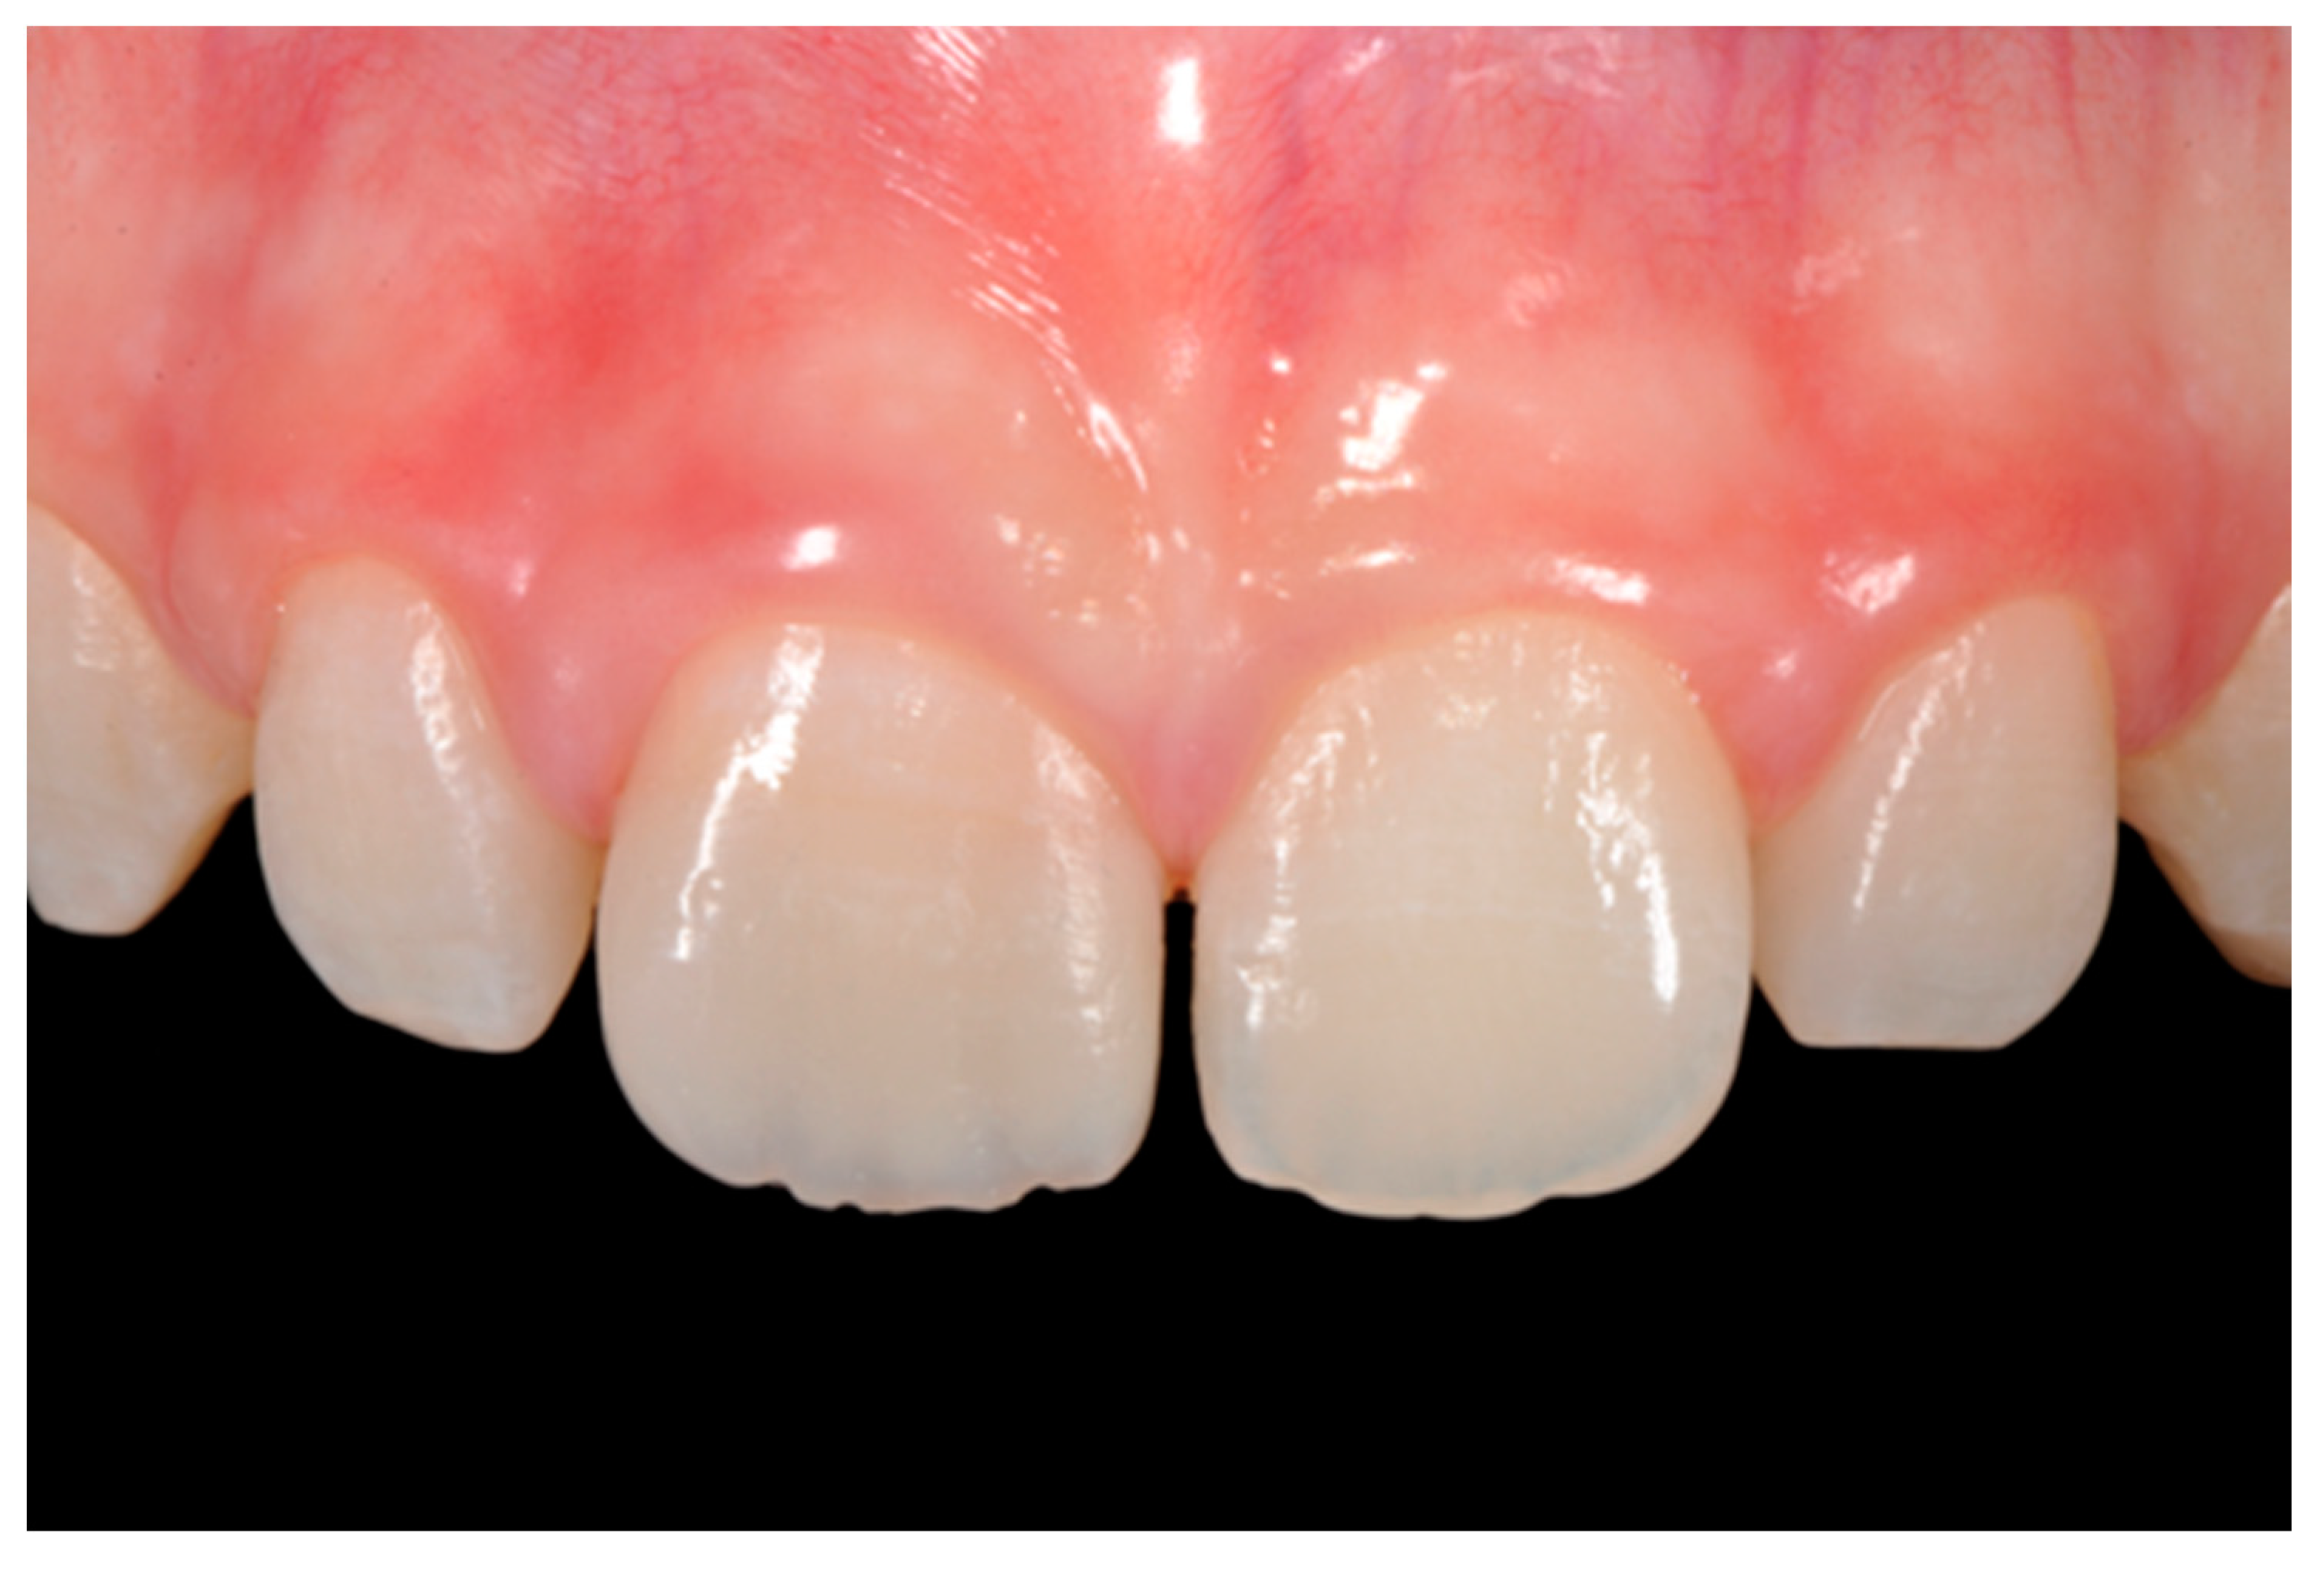

Figure 18.

Five years post-operative.

Finishing and polishing procedures were performed with a diamond bur (WL 268 014 Horico, Berlin, Germany), silicone points (Identoflex, Kerr, Bioggio, Switzerland) brushes (Jiffy Goat Air Brushes, Ultradent Products, South Jordan, UT, USA), and diamond pastes (Diamond Polish Mint, Ultradent Products, South Jordan, UT, USA) (Figure 13 and Figure 14). Satisfactory clinical and radiographic outcome was considered satisfactory at 3-months, 1-year, and 5-years post-operative (Figure 15, Figure 16, Figure 17, Figure 18 and Figure 19).